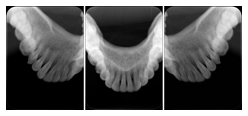

2. A patient requests cosmetic surgery to enhance their facial appearance. The case requires consultation between an orthodontist in New York and an oral surgeon in California. The cephalometric series of 2D projections constructed from a volumetric CT data set that is used for the discussion is arranged by a Structured Display for transfer between the two practitioners.

Cephalometric Series Structured Display

Figure OO-2. Cephalometric Series Structured Display